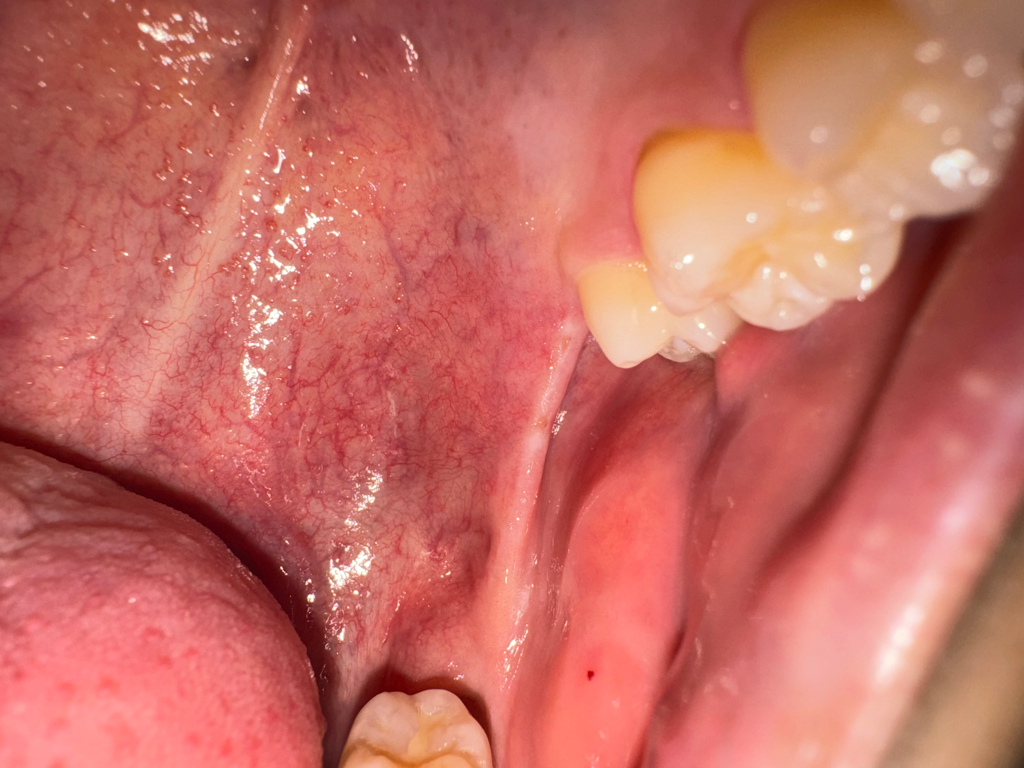

왼쪽 위아래 사랑니가 나야할 자리에 위아래로 연결된 끈 같은게 있는데 한 두달전부터 입벌릴때마다 땡기고 아픕니다. 오른쪽 아래어금니 크라운을 씌울 때 입을 계속 벌리고있었는데 그 때부터 의식하게돼서그런지 자꾸 신경쓰입니다. 사랑니가 나는 자리에도 약간 꺼끌꺼끌하게 상처같은게 나있는 것 같아요(혀로 만지면 느껴집니다.) 입을 최대한 크게 벌리면 저 끈같은게 끊어질 듯 아프고 사진도 자세히 보시면 말씀드린 끈같은것에 노란색 고른같은게 있어보입니다. 구강암같은 것일까요...? 치과에서는 별 말씀 없으셨었습니다.

1. 해당 구조는 pterygomandibular raphe라고 하며 정상 구조물입니다.

3. 노란색은 구강 내 지방조직 내지는 염증으로 추측됩니다.